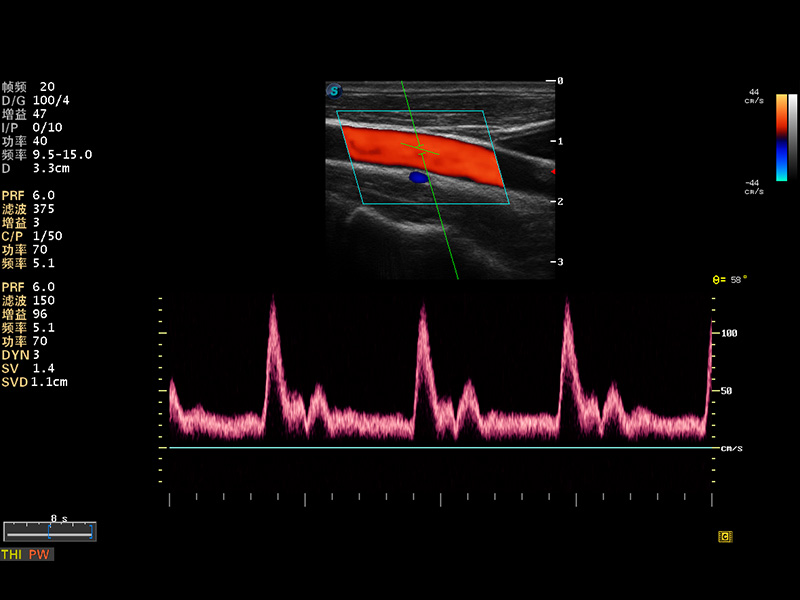

S8 EXP便携式彩色多普勒超声诊断仪是银河集团官网研发的高端全身应用型便携彩超。高通道的VIS平台融合可视化(Visual)、智能化(Intelligent)和人性化(Smart)的特点,配以银河集团官网自主研发生产的探头大家族,使您能够快速、准确的获得病人信息,提高工作效率的同时减轻疲劳。

成像技术

多波束形成器

μ-Scan微米成像

谐波成像

实时宽景成像

空间复合成像